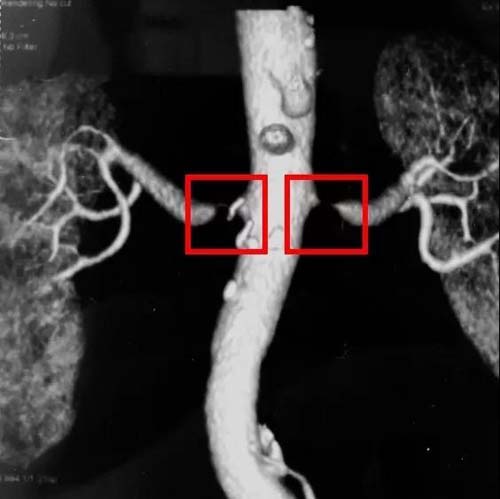

CT显示双侧肾动脉狭窄

CT可以看到双侧肾的大小、肾动脉狭窄的位置及程度、肾动脉开口的位置,便于制定处理方案。如果患者肾功能不好,进行CT血管造影则存在使患者病情恶化的风险。

肾动脉狭窄引起肾脏体积缩小